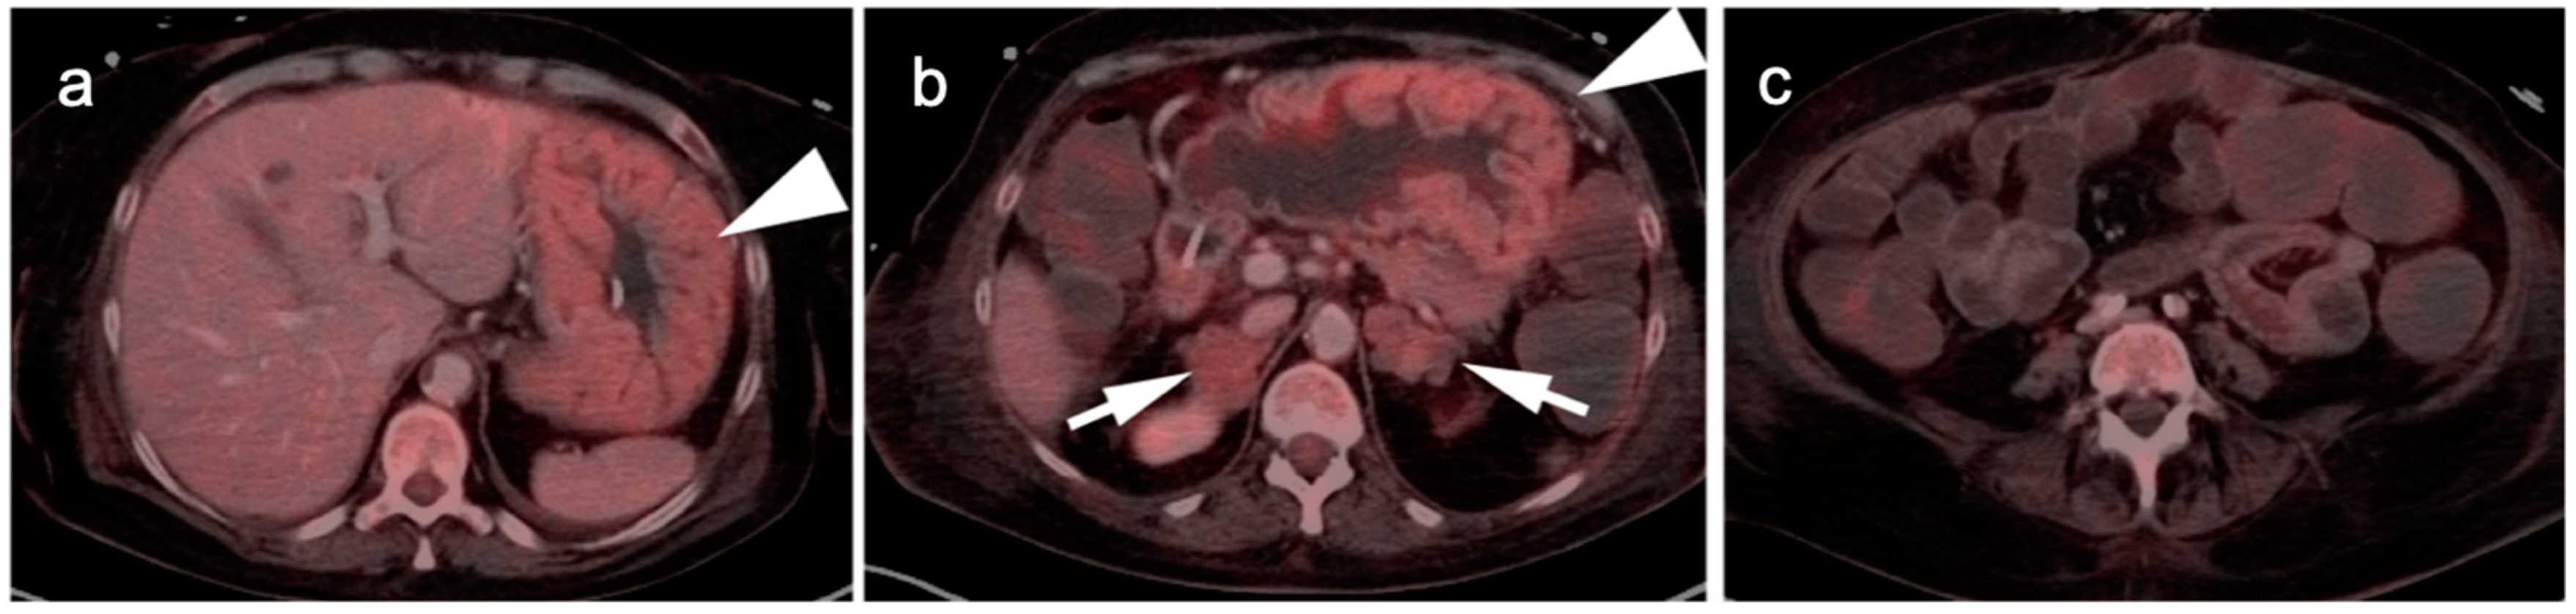

3. Gastrointestinal Stromal Tumor (GIST)